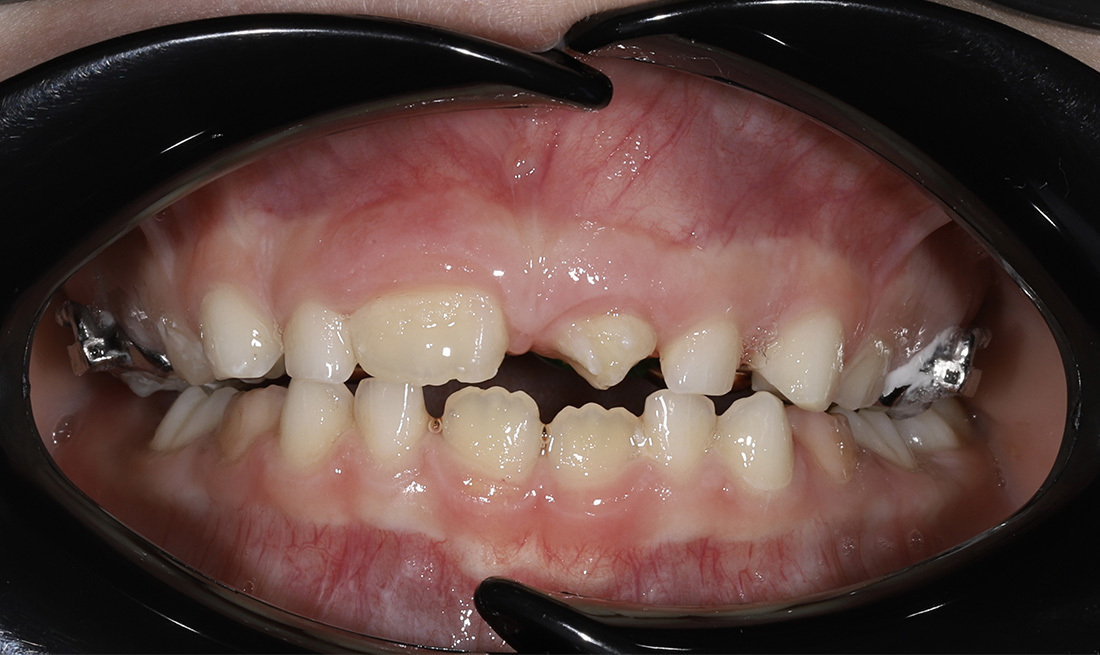

Комплексное ортодонтическое лечение у девушки с множественными нарушениями прикуса на фоне врождённой адентии боковых резцов